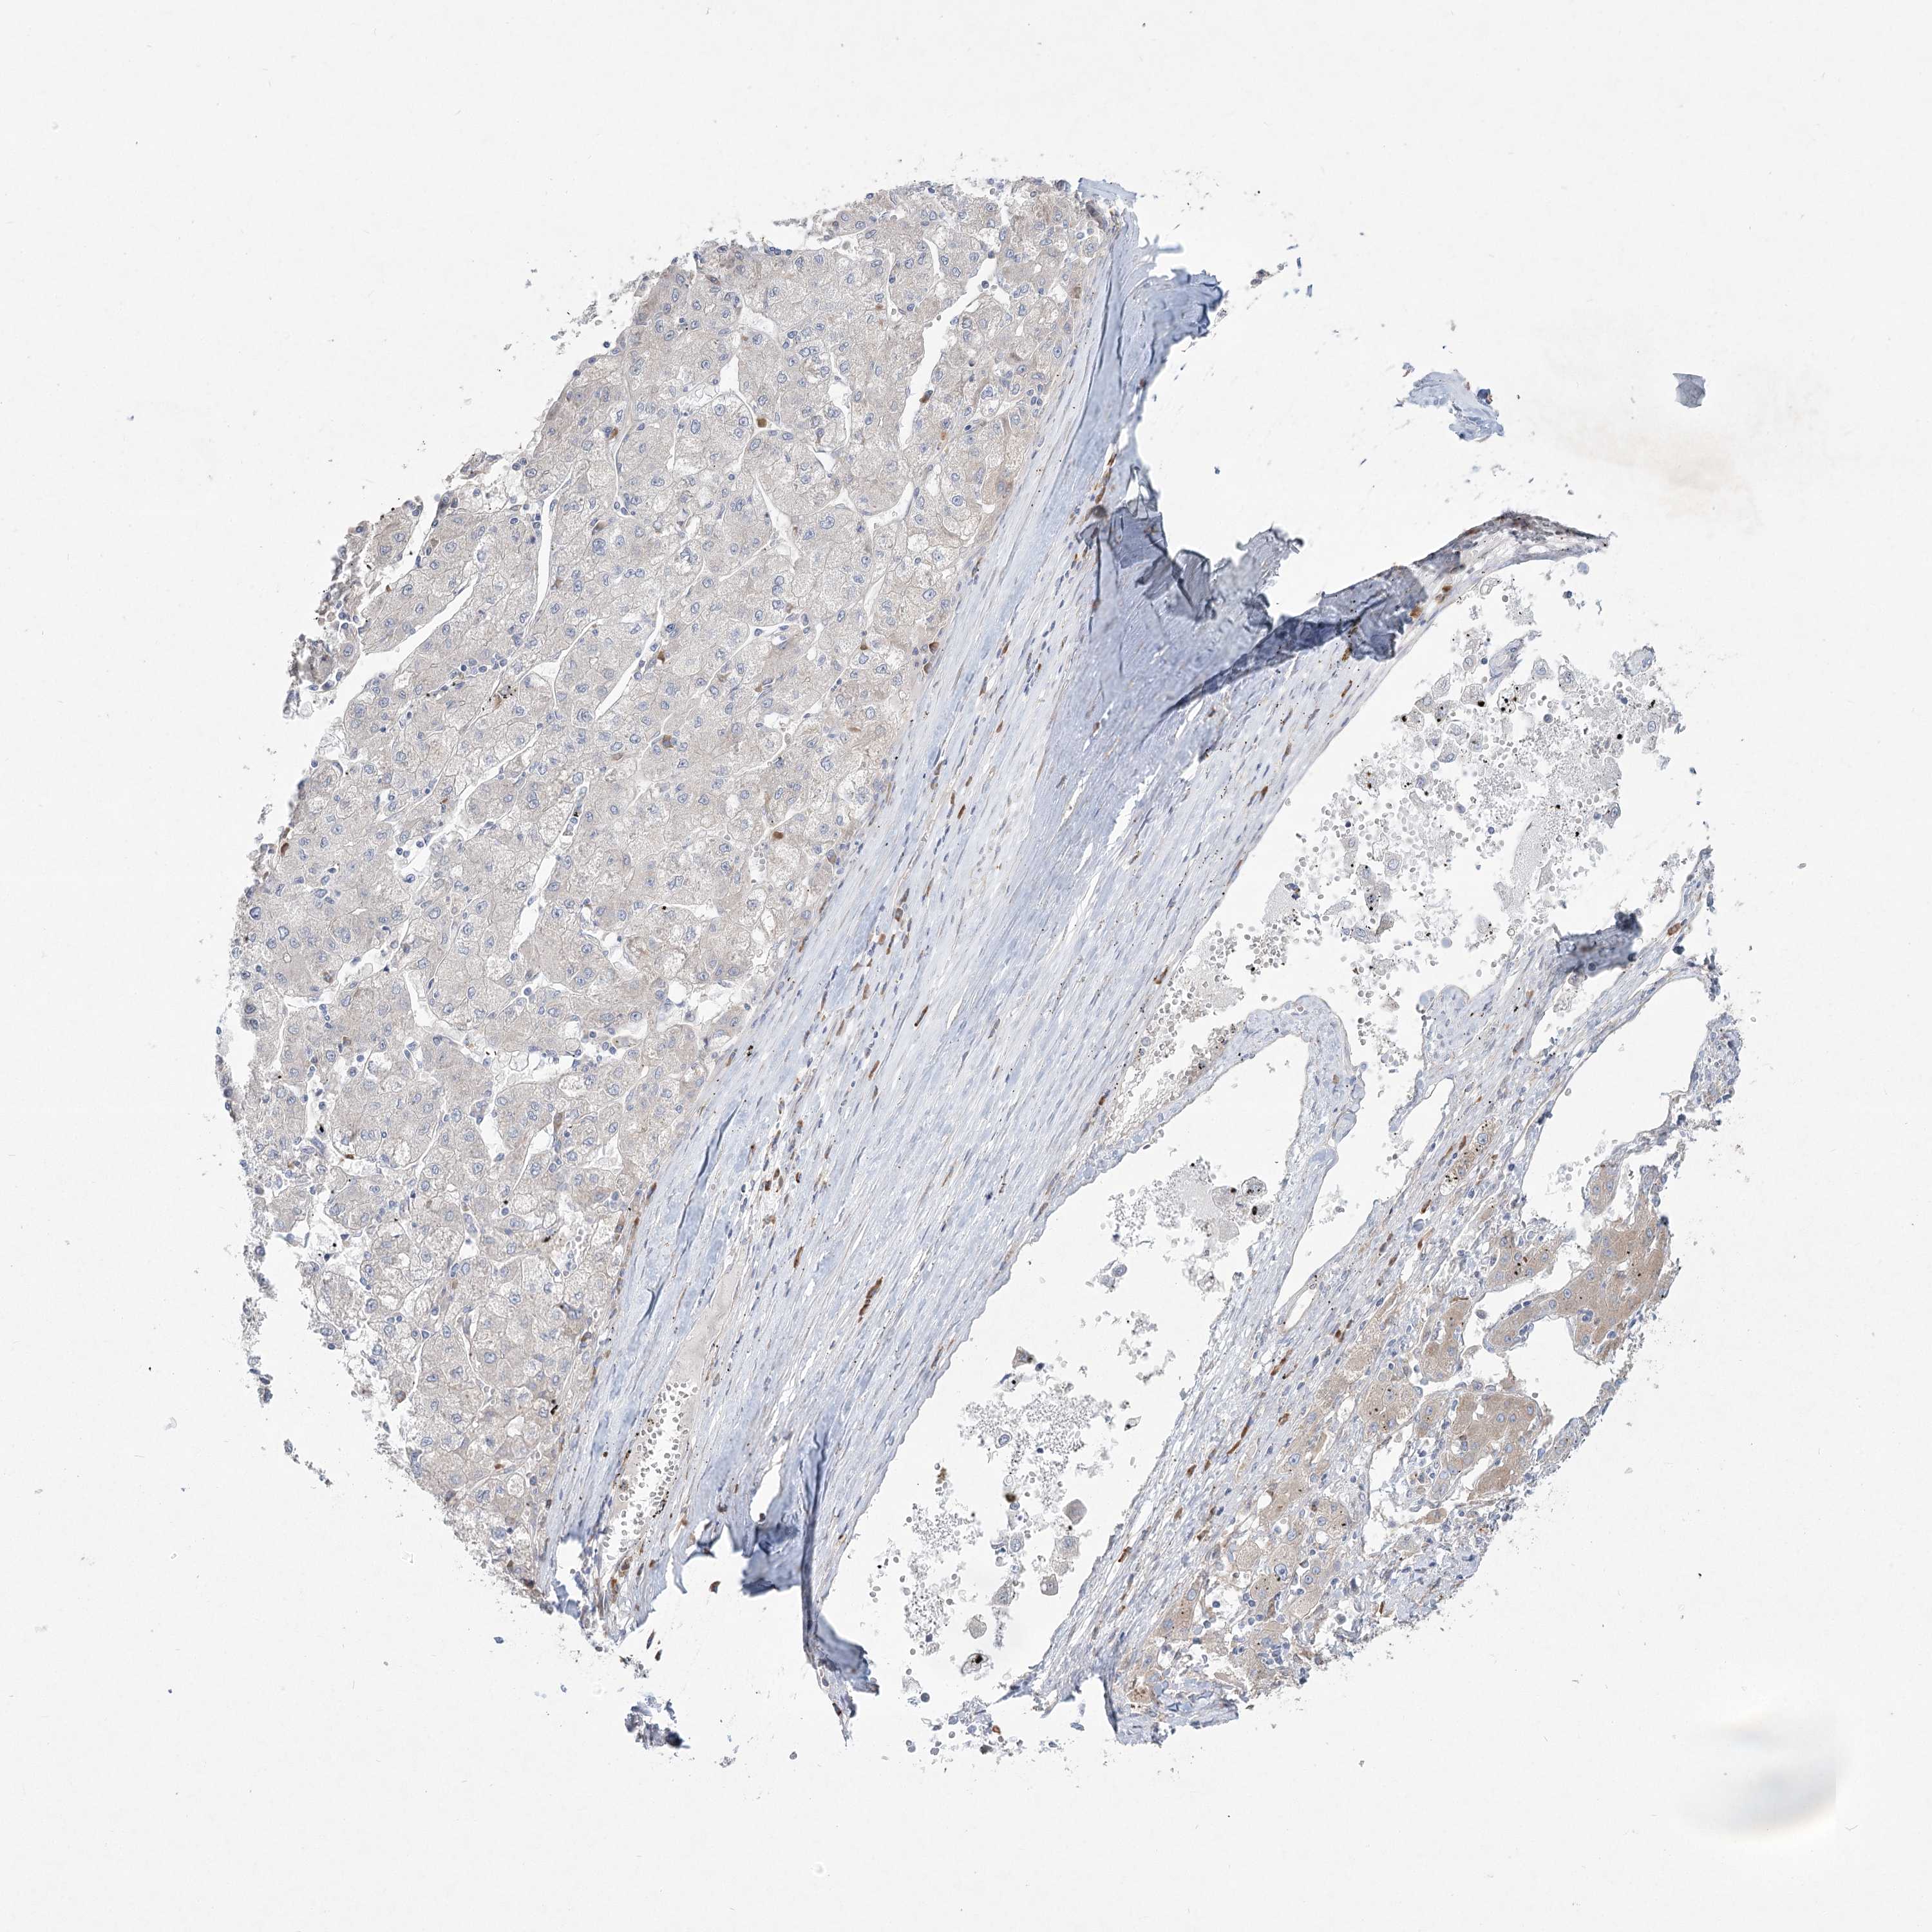

LIVER CANCER - Protein expressioni

A mouse-over function shows sample information and annotation data. Click on an image to view it in a full screen mode. Samples can be filtered based on level of antibody staining by selecting one or several of the following categories: high, medium, low and not detected. The assay and annotation is described here.

Note that samples used for immunohistochemistry by the Human Protein Atlas do not correspond to samples in the TCGA dataset.

Antibody stainingi

Antibody staining in the annotated cell types in the current human tissue is reported as not detected, low, medium, or high, based on conventional immunohistochemistry profiling in selected tissues. This score is based on the combination of the staining intensity and fraction of stained cells.

Each image is clickable and will lead to virtual microscopy that enables deeper exploration of all samples and also displays staining intensity scores, fraction scores and subcellular localization as well as patient and tissue information for each sample.

Antibody HPA036342

Antibody HPA036343

Staining

High

Medium

Low

Not detected

Intensity

Strong

Moderate

Weak

Negative

Quantity

>75%

75%-25%

<25%

None

Location

Nuclear

Cytoplasmic/membranous

Cytoplasmic/membranous,nuclear

Cholangiocarcinoma

Carcinoma, Hepatocellular, NOS